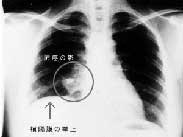

• 老年人肺膿腫

628健康網為您分享有關老年人肺膿腫的癥狀,老年人肺膿腫的治療方法,老年人肺膿腫的預防知識,老年人肺膿腫的癥狀圖片,老...